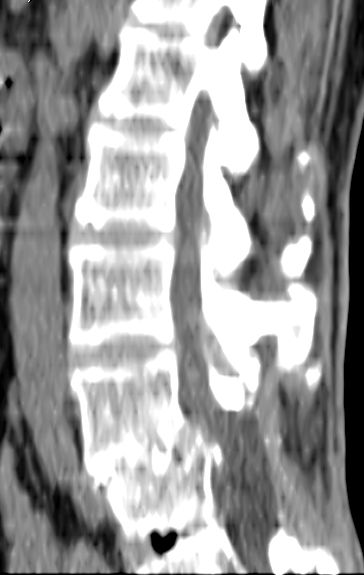

以下是引用余辉在2007-9-4 21:00:00的发言:[br]椎体棘突有点异常(像是被切割了),不知有否手术史,如椎体融合术等。单纯的退行性变可以出现椎间隙变窄,但同时一般会出现椎体上下缘的硬化增生,且椎体间完全融合的机率更小,本例椎体完全融合且椎体上下皮质缘破坏掉了,如果没有手术史,就应该考虑椎间盘炎性病变了,且椎体棘突及棘间韧带的变化也并不是不支持这个,多数小关节也融合了,且其形态也容易让人联想到如强脊炎及类风关等病变。[br][br][本贴已被 余辉 于 2007-9-4 21:03:55 修改过]

以下是引用chry3在2007-9-4 20:42:00的发言:[br]椎间盘病史?是什么样的病史,无双下肢放射痛,那就不是椎间盘突出了。是感染、什么性质的?[br]从图象看椎间隙消失,椎间盘组织未见,锥体滑脱是因为椎间盘溶解造成的[br]l4、5椎体骨质结构未见异常,l5上缘是l4的长期压迫所致[br]还是考虑椎间盘感染,结核。[br]